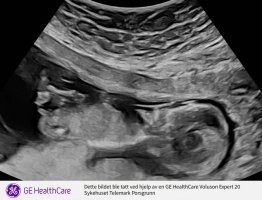

Tipper det her er en liten guttHei! Var på privat ultralyd uke 14+ 3, men jordmor turte ikke å konkludere med kjønn enda. Skal sies at hun først var veldig sikker på gutt, men ble mer og mer usikker etterhvert som hun så, og derfor ikke turte å konkludere. Er ingen ekspert på Nub-teorien, men syns jeg ser tydelig gutt på disse bildene? Blir bare veldig usikker når jordmor mente det fortsatt kan være jente, og en hoven klitoris. Hva tenker dere? hilsen alt for nysgjerrig mamma![]()